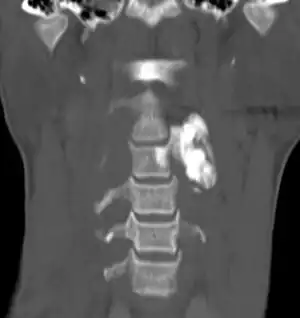

| Osteoblastoma in neck | |

Osteoblastoma is a rare noncancerous bone tumor, of the osteogenic type.[2][3][1] It usually presents with a dull pain in the back.[1]

Generaly, osteoblastomas present between the age of 20 and 40 years.[4] Around 40% are located in the spine, and over half have associated scoliosis.[4]

When diagnosing osteoblastoma, the preliminary radiologic workup should consist of radiography of the site of the patient's pain. However, computed tomography (CT) is often necessary to support clinical and plain radiographic findings suggestive of osteoblastoma and to better define the margins of the lesion for potential surgery. CT scans are best used for the further characterization of the lesion with regard to the presence of a nidus and matrix mineralization. MRI aids in detection of nonspecific reactive marrow and soft tissue edema, and MRI best defines soft tissue extension, although this finding is not typical of osteoblastoma. Bone scintigraphy (bone scan) demonstrates abnormal radiotracer accumulation at the affected site, substantiating clinical suspicion, but this finding is not specific for osteoblastoma.